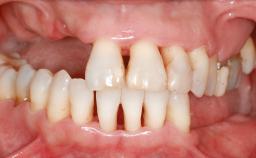

A woman in her mid-fifties was referred by a dental student for dental implant placement. Both posterior segments of the mandible had been edentulous for more than 4 years, the only residual tooth being the right lower first premolar. The patient had used a removable partial denture but was not entirely satisfied with its function. The clinical examination revealed a sharp edentulous ridge in both posterior segments of the mandible, and the patient was told that it would not be possible to insert implants into this thin edentulous ridge without significant augmentation of the alveolar ridge. Her medical history revealed no significant findings and no underlying disease that might have complicated surgical procedures. During the presurgical examination, the patient reported that she was a little apprehensive about bone grafting. After being informed about the surgical procedures and potential postoperative complications, she accepted the proposed surgical plan of bone grafting and subsequent placement of implants.